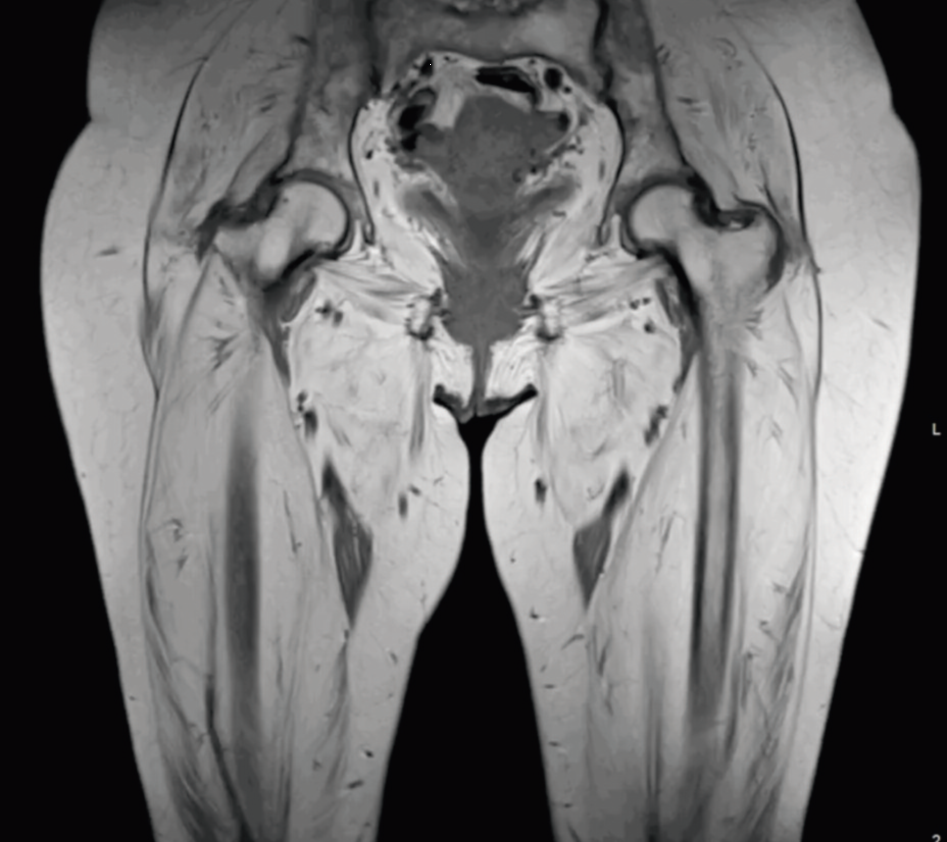

定期通过 MRI 随访,能够获取肌肉病变活动性的关键信息,并能识别因肌肉已完全被脂肪替代而不再适合继续使用免疫抑制治疗的病例(图 1-2)。

图 1. 冠状位 T1 加权图像显示双侧大腿及骨盆肌群弥漫性重度脂肪浸润,双侧股四头肌近乎完全脂肪替代